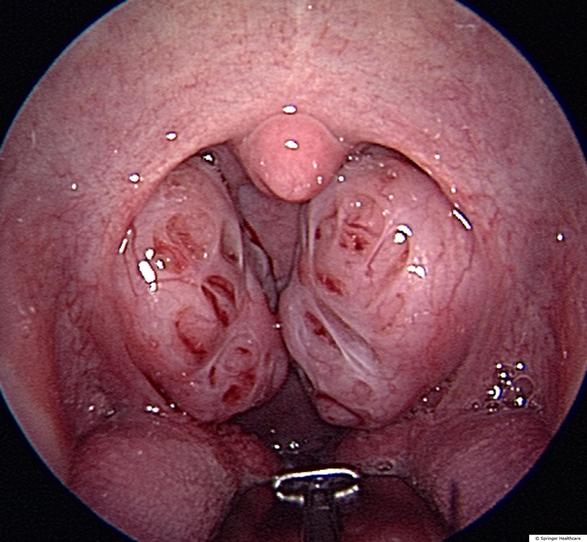

慢性扁桃体炎,扁桃体肥大

正常的扁桃体